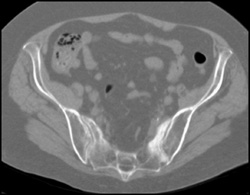

Heterotopic Ossifications